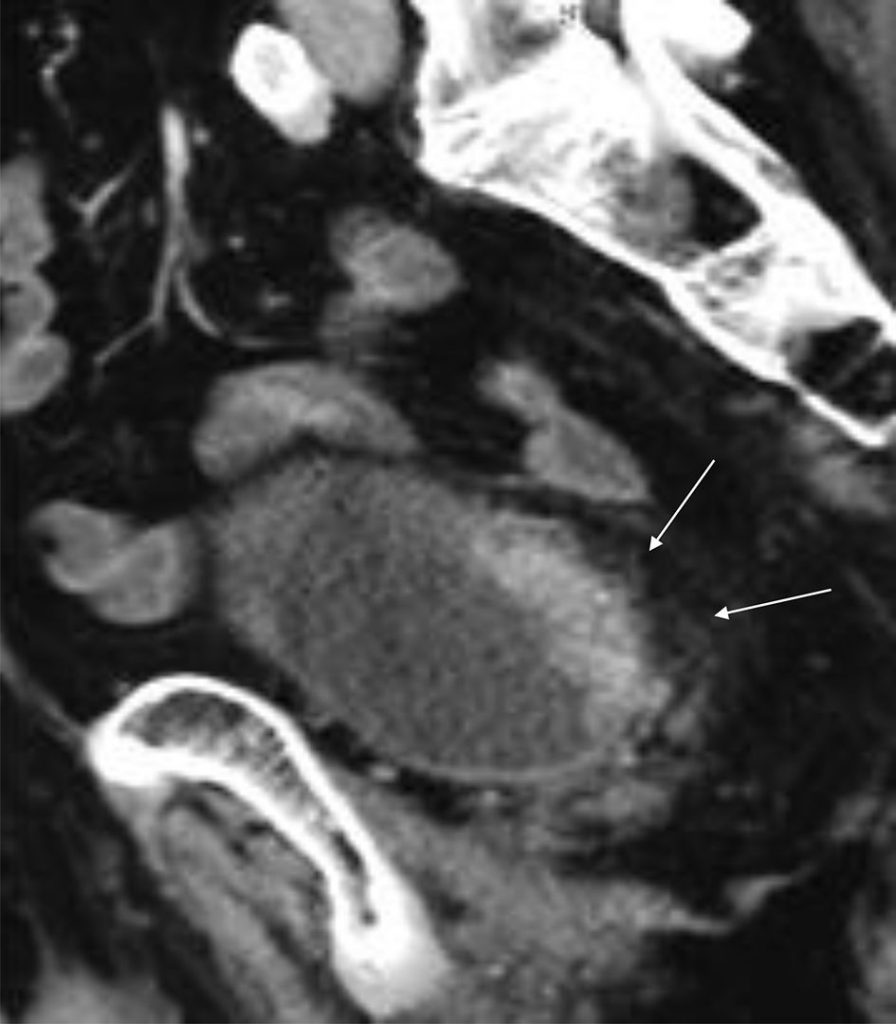

La TDM ne détecte qu’un envahissement massif de la graisse de l’espace périvésical (figure 33.3).

Fig. 33.3 TDM avec injection de produit de contraste iodé au temps portal et reconstruction sagittale oblique.

La tumeur est infiltrante car elle envahit la graisse périvésicale adjacente (flèches). Le rectosigmoïde n’est pas envahi.

Source : CERF, CNEBMN, 2022.

L’envahissement des structures digestives est difficile à identifier.